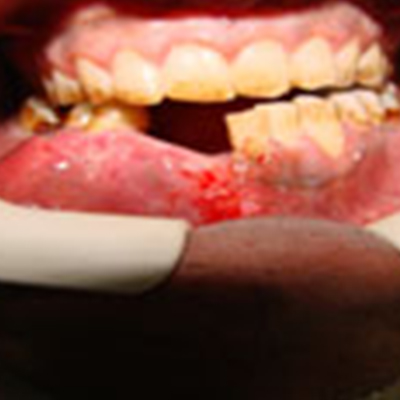

Tumor surgery

There a lot of tumors that varies from less than 1 cm in diameter and length to very extensive in size that requires more than hemimandibulectomy which means resection of more than half of the jaw, depending on the size and aggressiveness of the tumor lesion.